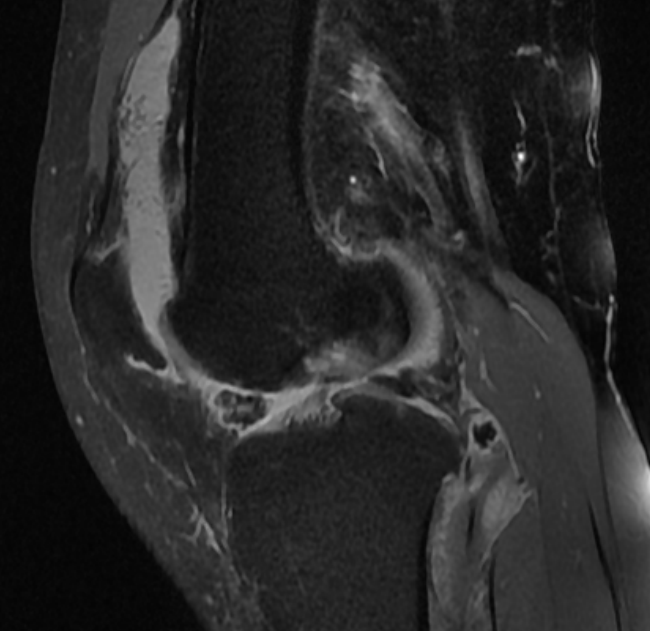

术前影像

就在彭阿姨一筹莫展之际,她来到了郴州市中医医院骨伤科求医。经完善右膝关节CT、MRI检查后,彭阿姨确诊为膝关节骨性关节炎中期,关节内已形成游离体,伴随关节软骨损伤,属于 “保膝” 治疗的适宜指征。